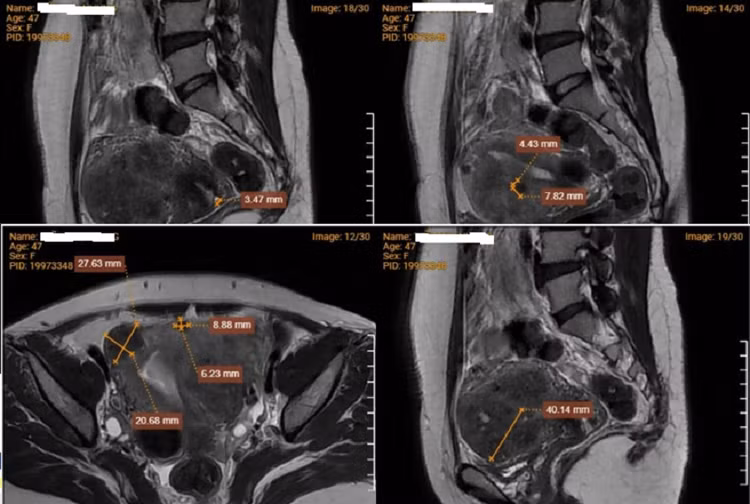

| Hình ảnh chụp MRI cho thấy bệnh nhân mắc đa u xơ tử cung. Ảnh BVCC |

Kết quả siêu âm đầu dò âm đạo, kích thước tử cung tăng; nội mạc tử cung dày 7,5mm. Cơ tử cung có cấu trúc không đồng nhất, thành trước và thành sau không cân xứng, thành trước có cấu trúc giảm âm lan tỏa dạng sợi sọc kích thước 71x50mm, ranh giới không rõ. Rải rác cơ tử cung có vài cấu trúc giảm âm, bờ đều, ranh giới rõ, không tăng sinh mạch trên siêu âm Doppler, lớn nhất kích thước 30x34mm…

Dựa vào những kết quả đó, bác sĩ chẩn đoán bệnh nhân mắc đa nhân xơ tử cung và nghi ngờ mắc lạc nội mạc tử cung nên chỉ định làm thêm MRI, xoắn polyp cổ tử cung gửi giải phẫu bệnh.

Kết quả MRI tiểu khung cho thấy, hình ảnh bệnh cơ tuyến tử cung (adenomyosis) hay còn gọi là lạc nội mạc tử cung. Bên cạnh đó là đa u xơ tử cung (phân loại FIGO L4-5), nang Naboth cổ tử cung, nang nhỏ thành sau âm đạo.

Kết hợp với kết quả giải phẫu bệnh, bác sĩ xác định, bệnh nhân mắc lạc nội mạc tử cung, đa u xơ tử cung và polyp cổ tử cung. Bệnh nhân được nhập viện, phẫu thuật cắt tử cung bán phần.